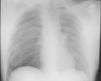

Varón de 30 años con antecedentes de neumotórax unilateral derecho hace 3 meses, que consultó por disnea y dolor en el hemitórax izquierdo de 3h de evolución. En la exploración se apreció taquipnea, la saturación de oxígeno era del 93% y las constantes, estables. La radiografía de tórax evidenció neumotórax izquierdo con desplazamiento mediastínico hacia hemitórax contralateral. Se colocó un tubo de drenaje de 18 F, maniobra durante la cual el paciente se quejó de dolor torácico de intensidad moderada. Se realizó la imagen de control (fig. 1). Se procedió al drenaje en el hemitórax derecho sin incidencias. En la nueva prueba radiológica se objetivó la reexpansión de ambos pulmones. Durante el ingreso se efectuó una tomografía axial computarizada (TAC), que mostró bullas paramediastínicas y apicales bilaterales, predominantemente izquierdas. Una vez completado el preoperatorio, se intervino al paciente mediante ampulectomía y pleurodesis mecánica de ambos pulmones en 2 tiempos. El postoperatorio transcurrió satisfactoriamente y se dio de alta al paciente a la semana de la intervención.

Destacamos la importancia de este caso por la forma de presentación, pues en la primera prueba de imagen no se observó el neumotórax existente en el lado contralateral, que sí se detectó en la radiografía de control realizada tras la colocación del tubo de drenaje. Esto nos lleva a plantear las siguientes consideraciones: